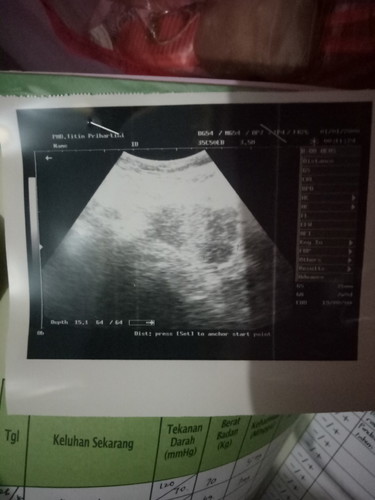

Wajar engga ya 7week masih penebalan rahim belum terlihat kantong rahim nya

bunda sekarang berarti berapa week ya. usg nya mirip sama punya saya tapi dokter saya bilang saya masih penebalan rahim saja

Wajar kok bun. Itu masih proses. Cek 3 minggu lagi. Saya jg kemarin gitu masih penebalan dinding rahim. Dan usia kandungan masih muda sekali 2 week. Disuruh balik ke dokter 3 minggu lgi. Udh ada kantong udh 8 week.

tapi bahaya gak si bun? aku soalnya anak pertama taunya pas 15minggu jd gak ngerasain bgini belum kelihatan dinding rahim nya.tadi sy usg 5minggu blm keliatan apa apa diblgnya penebalan rahim apa gitu. agak cemas drtd tp dibw rileks;' tgl 19 desember sy disuruh kontrol lagi ke Rs. krna pas anak pertama lahir prematur lahir 12/09/22 meninggal 26/09/22 di nicu. selesai nifas saya 22Oktober,27nya saya menstruasi, saya testpack garis 2 nya tgl 25 . itungan bidan 5minggu itungan dokter usg 4 brpa hr gitu td